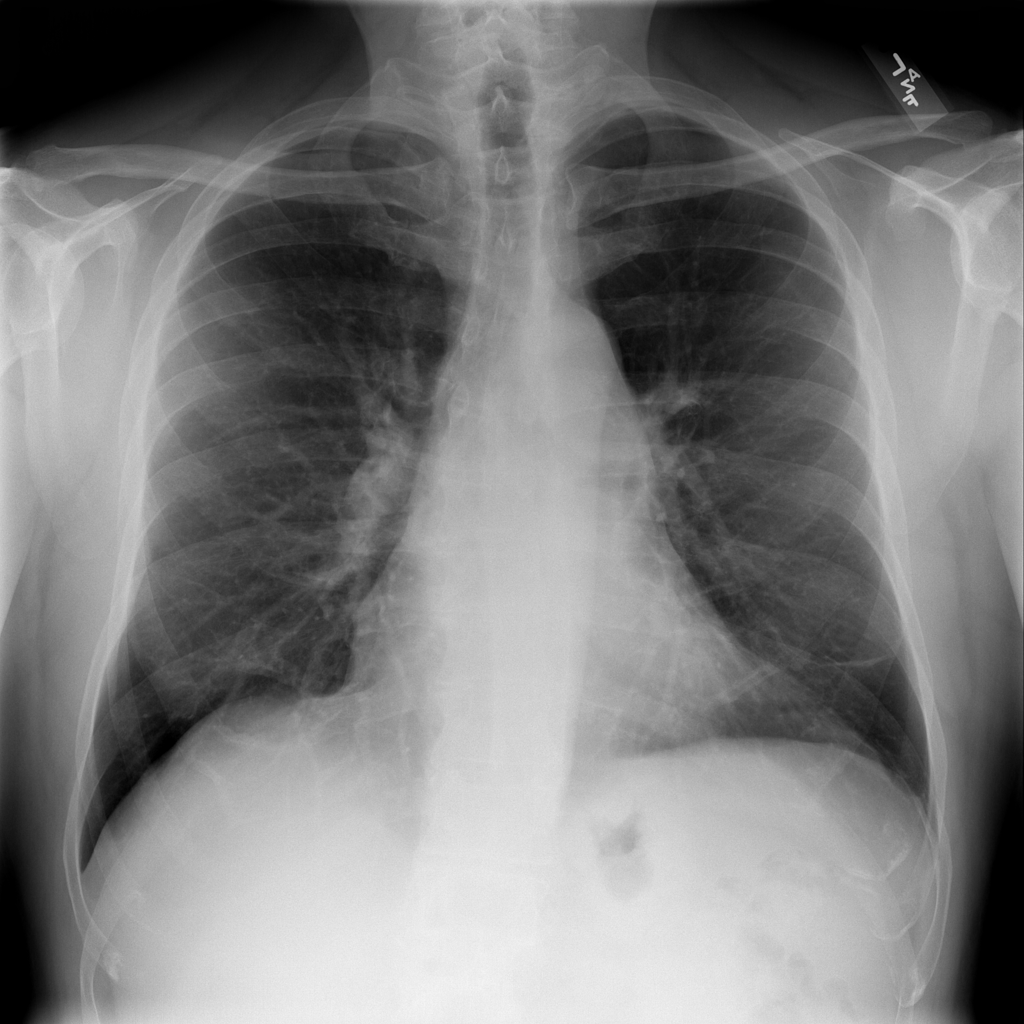

Nodule

A nodule is a small rounded opacity in the lung or chest field. It is a descriptive imaging finding that can be benign or more concerning depending on size, appearance, and context.

Showing up to 90 reference images for Nodule.

PAT-FB8F · IMG-000Nodule

PAT-FB8F · IMG-000

PA